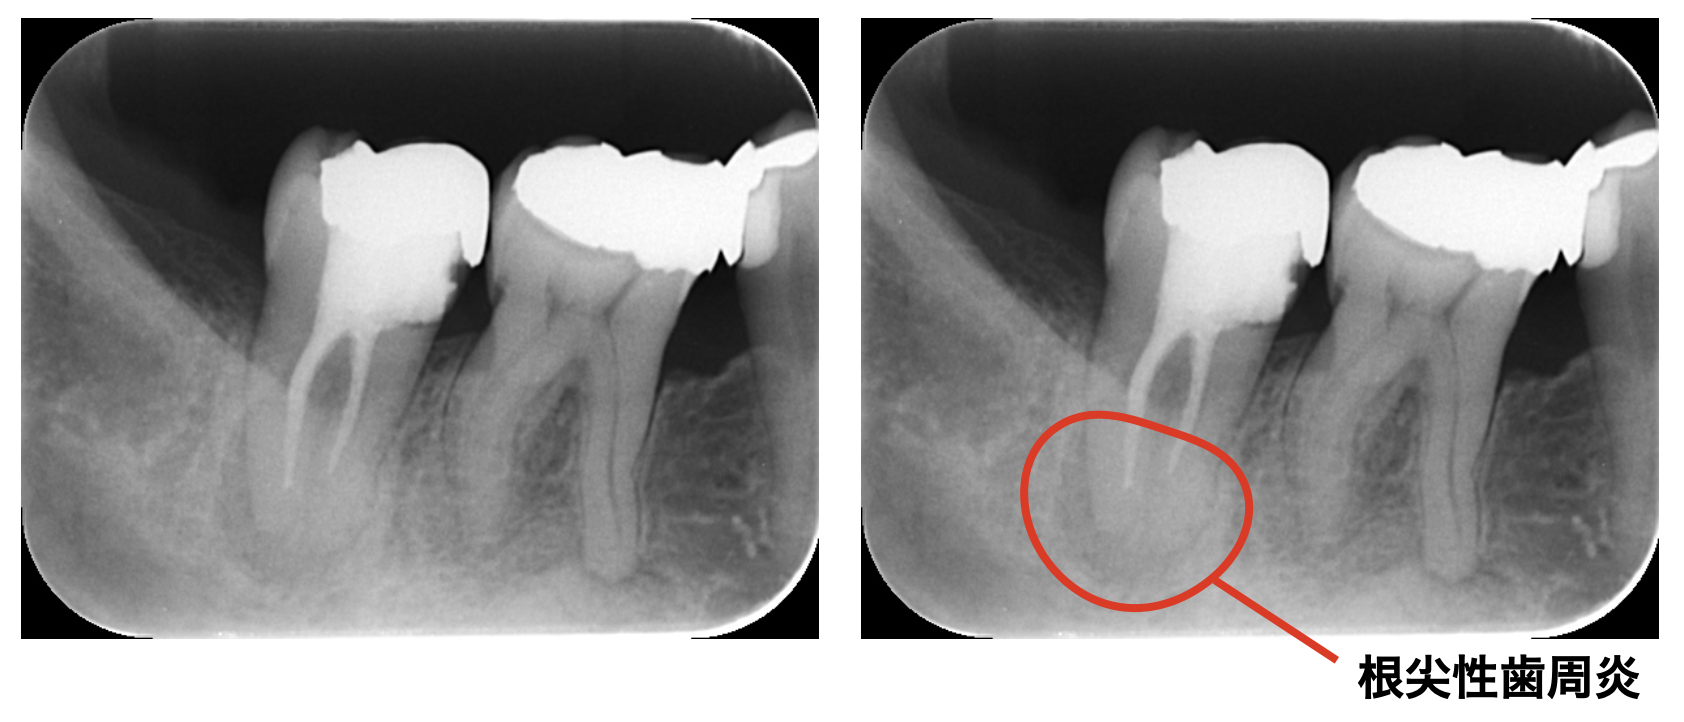

過去に治療を受けている歯の場合、神経が痛みに反応しているのではなく、歯の中が細菌によって感染しているため根の先に病気が出来てしまって痛みが出ていることが多いです。

これは「根尖性歯周炎」と呼ばれていて、痛みを伴うものもあれば、無症状に進行するものもあります。